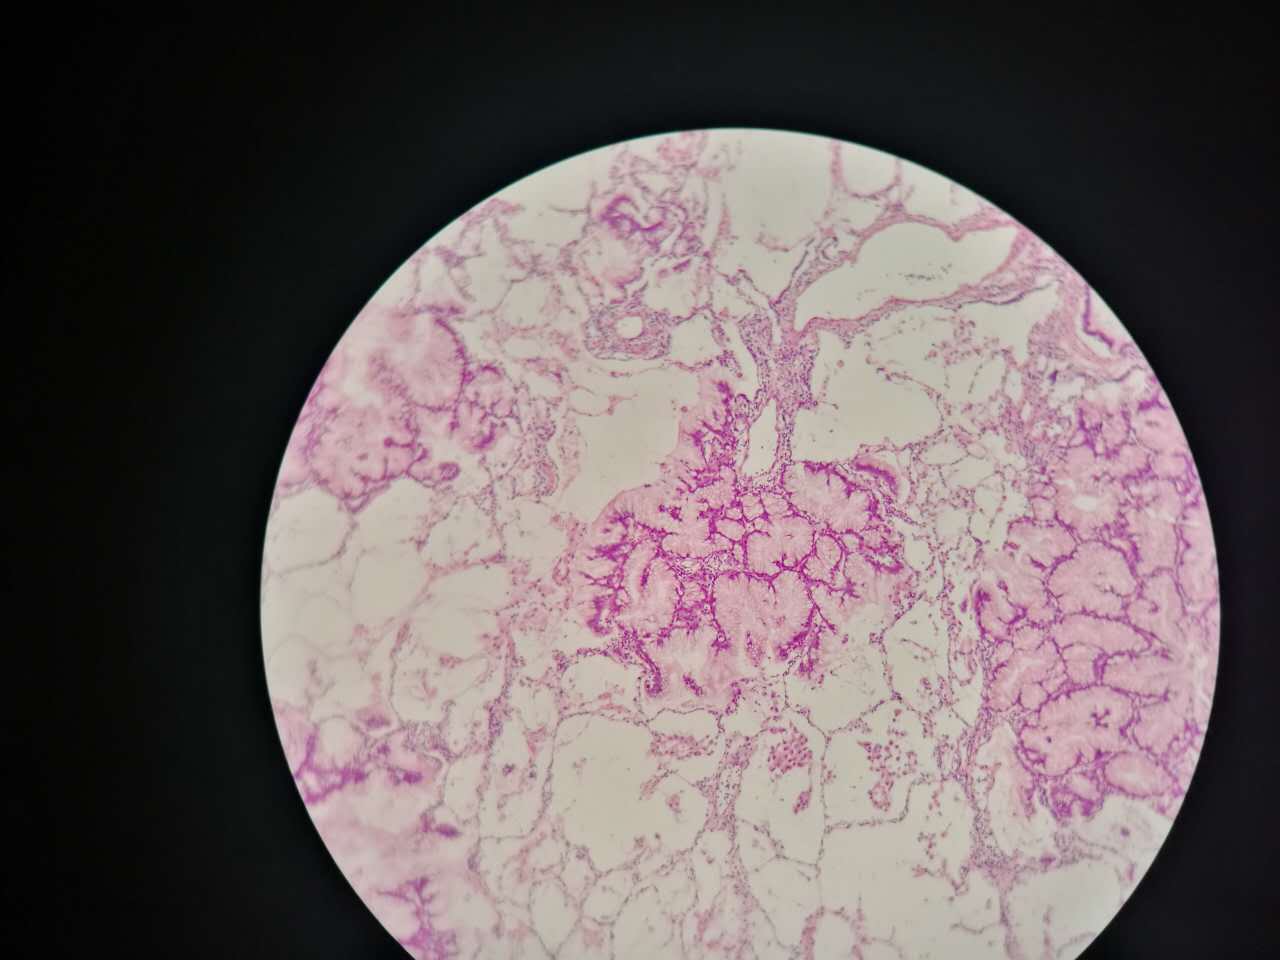

这个是早期结节状的粘液型腺癌

随着粘液近距离播散

早期粘液漂散也是近距离的,右侧肺泡里干净,没粘液,粘液产量有限,并且互相有黏连牵制。

所以结节性粘液腺癌边界一般较清楚

这个细支气管,一半癌浸润

中央有个肺血管,说明破坏力不强